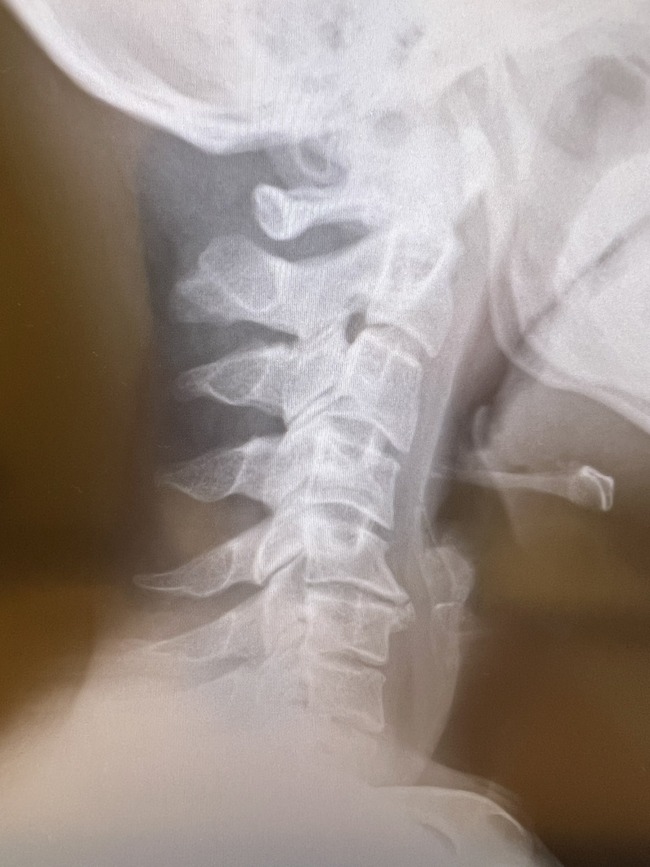

首終わりし男 pic.twitter.com/Yt4rrCtErO

ハイパーストレートネッカー純

ストレートどころか逆に曲がってないか・・・?

スマホを見たりする様な首を傾けた姿勢を長時間してると

このストレートネックになりやすいんだっけ

頭痛や肩こりが酷くなる

>>15

本来緩やかにカーブしてるべき骨がまっすぐというか

むしろ微妙に逆向きにカーブしてる

- ストレートというか逆に曲がっとる

ストーレートネック、血行不良で認知機能に影響でたな。人の言葉聞こえてるのに理解できない。文字読んでも頭に入らない。集中力が極端に低下すると、こういう症状に陥るらしい。